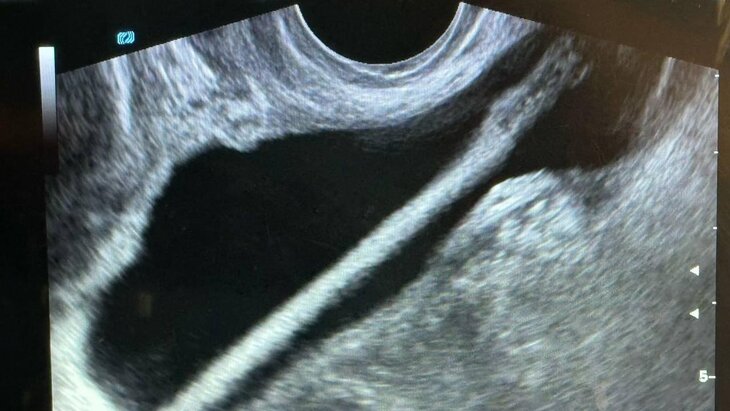

Заведующий отделением Петр Сысоев рассказал, что после проведения УЗИ пациентке провели эндоскопическую операцию, в ходе которой инородное тело было удалено без осложнений. Сейчас женщина уже выписана домой.